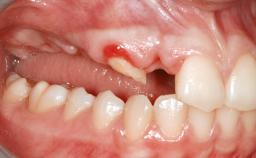

A 47-year-old Caucasian woman with a single-tooth edentulous space at the site of the left maxillary canine was referred for treatment. She had undergone traumatic extraction of this impacted canine several months before referral. Her chief complaint was the dissatisfying appearance of her smile. The patient desired a stable and esthetic rehabilitation of the site. Her dental history showed no evidence of periodontal disease or bruxism. She had no systemic diseases, was not taking any medications, and did not smoke. The extraoral examination revealed a high lip line and an inadequate soft-tissue volume at the defective canine site. Large black triangles were visible between the canine and its adjacent teeth.

Soft Tissue Anatomy Intact Defective

Bone Volume Horizontally and vertically sufficient Horizontally deficient Deficient vertically or deficient vertically AND horizontally

Bone Volume Deficient vertically or deficient vertically AND horizontally